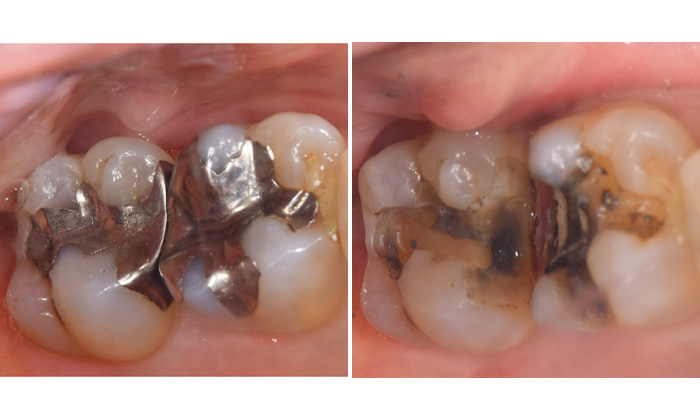

写真では10年以上前にいれた銀歯がしみるという症状があったためはずして中を確認すると、大きく虫歯になっていました。

麻布十番歯科で銀歯が虫歯になってしまった症例の口腔内写真